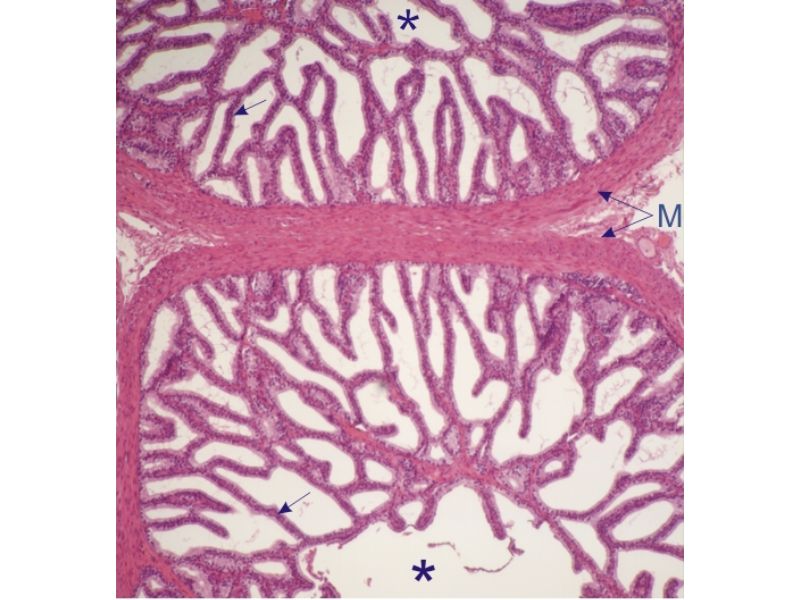

Vesicula seminalis

Slide 81Vesicula seminalis

- Mucosa

- Epithelium

- Lamina propria

- Muscle layer

Mucosa

- Lumen

- Irregular

- Store secretions

- Pseudostratified columnar epithelium

- Lamina propria

- Contains AVL

- Folded mucosa ^^ surface area

Muscle layer

- Inner circular

- Outer longitudinal